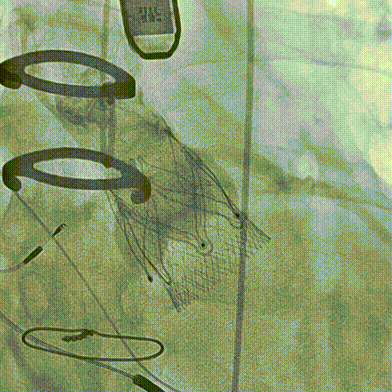

2026年伊始,TaurusTrio经导管主动脉瓣系统在武汉大学人民医院,中国科学技术大学附属第一医院,安徽医科大学第一附属医院,安徽医科大学第一附属医院北区,首都医科大学附属北京安贞医院南充医院,海南省人民医院等多家临床中心成功开展上市后全国首批植入。这不仅是TaurusTrio正式走向广泛临床应用的重要里程碑,更标志着中国单纯主动脉瓣反流介入治疗正式迈入了“心键合璧”的全新纪元。

首植告捷,新程启幕。TaurusTrio的成功获批与全国首批植入的正式启动,不仅是沛嘉医疗深耕结构性心脏病领域、坚持自主创新与临床需求深度融合的重要里程碑,更是我国结构性心脏病介入诊疗领域的关键技术突破。